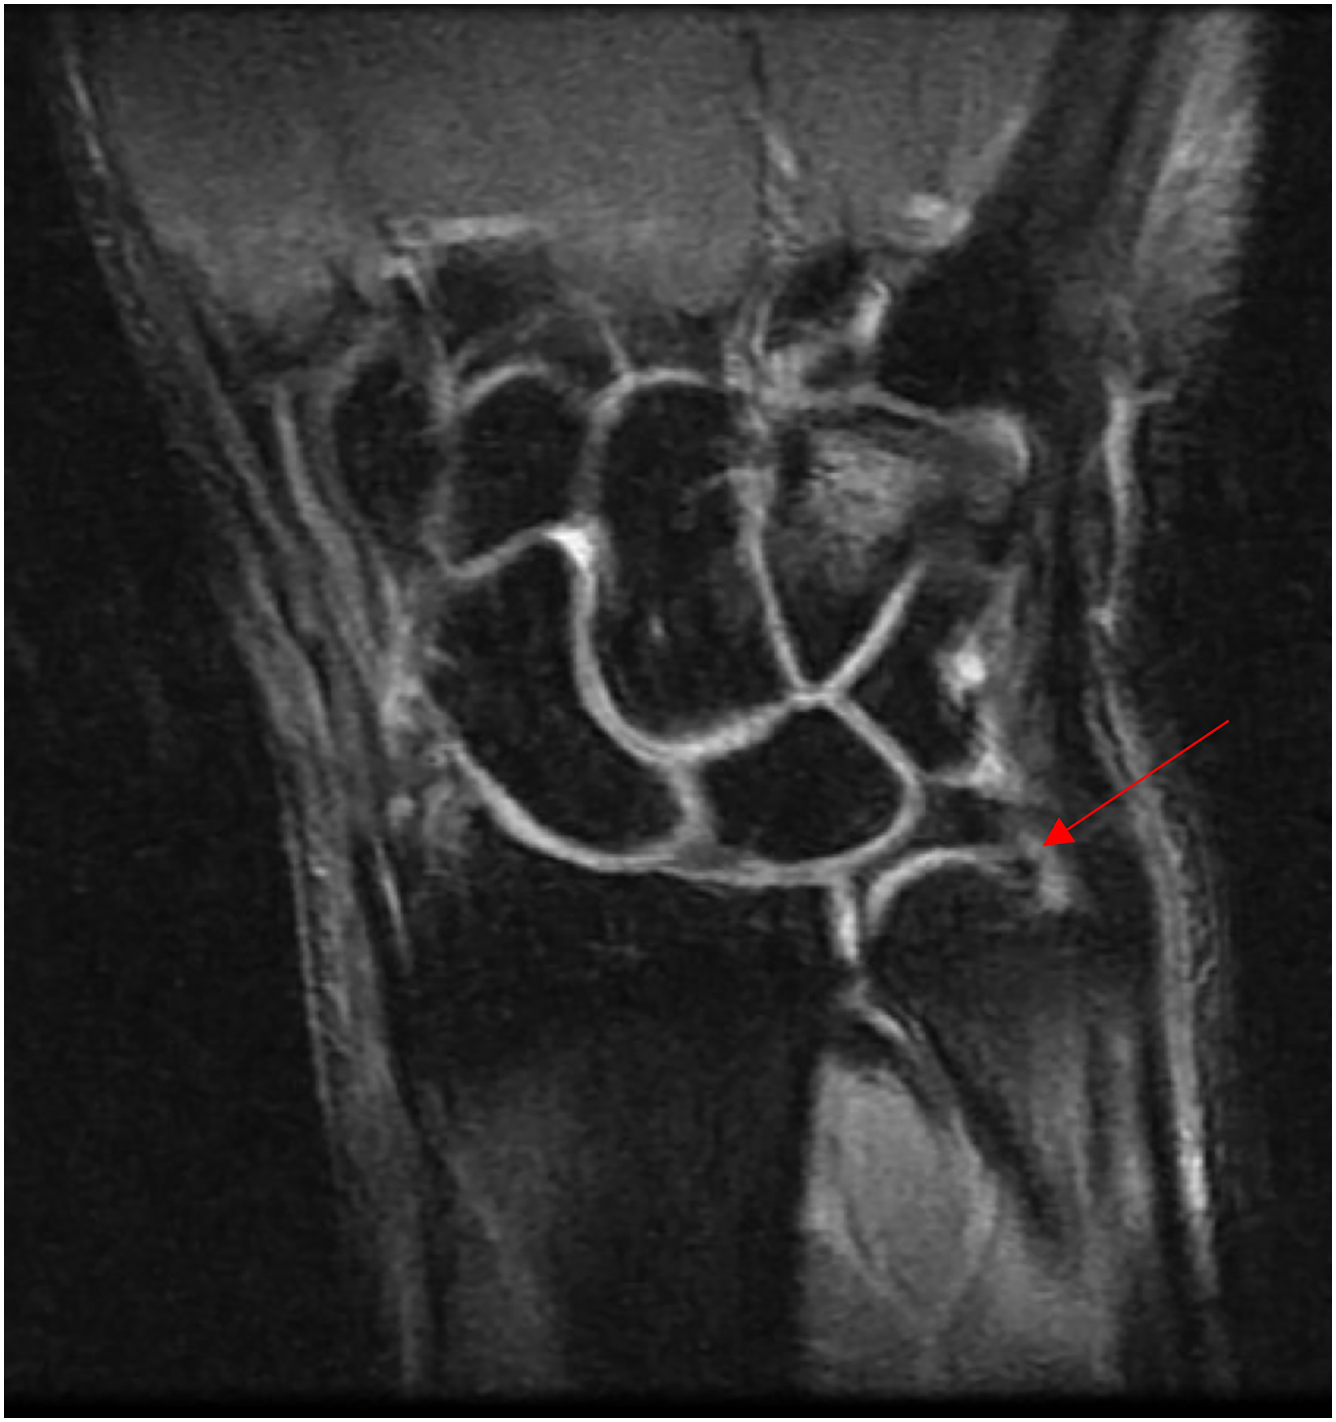

Plain radiographs are important for initial imaging evaluation, as they allow for an assessment of ulnar variance, DRUJ congruity, as well as an ulnar styloid avulsion that could suggest an acute injury. Contralateral radiographs may be useful for comparison. Assessment of ulnar variance is typically performed on a PA radiograph with the forearm in neutral, shoulder in 90° of abduction, and elbow in 90° of flexion. MRI may also be performed for further assessment of the TFCC for central or peripheral tears, keeping in mind that 3 T MRI scans demonstrate greater sensitivity, specificity, and accuracy compared to 1.5 T MRI scans ( Fig. 7 ). Magnetic resonance arthrography (MRA) has also been increasingly utilized, as increased accuracy has been found in diagnosis of central and peripheral TFCC tears among patients receiving MRA versus MRI. The gold standard for diagnosis, however, is direct visualization and examination via arthroscopy.